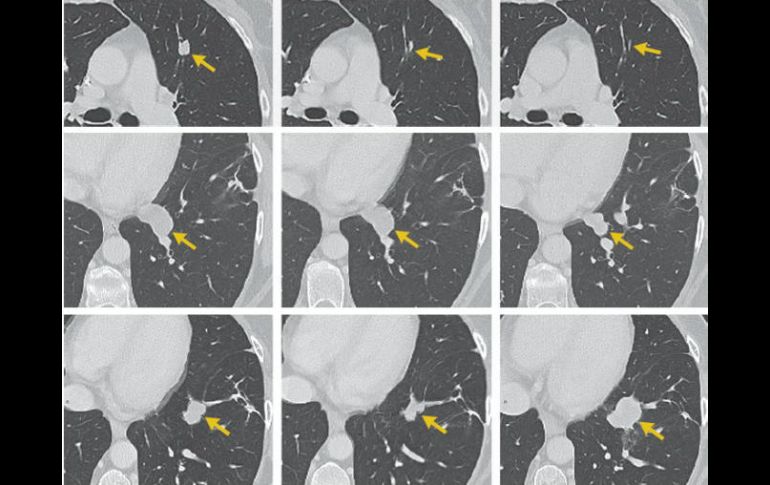

Más de un tercio de enfermos avanzados de linfoma no mostraron señales de la enfermedad seis meses después del tratamiento. TWITTER / @KitePharma

LOS ÁNGELES, ESTADOS UNIDOS (28/FEB/2017).- Una terapia genética experimental que convierte las células sanguíneas del paciente en agresoras contra el cáncer resultó eficaz en un importante estudio en el que más de un tercio de enfermos avanzados de linfoma no mostraron señales de la enfermedad seis meses después del tratamiento, dijo su fabricante el martes.

En el 82% de los pacientes, el cáncer se redujo al menos a la mitad en algún momento del estudio.

Una señal alentadora: el número en remisión total a los seis meses(36 prácticamente no difiere de los resultados parciales a los tres meses, lo cual indica que este tratamiento en una sola sesión podría tener beneficios duraderos para los que responde bien.

Los enfermos padecían uno de tres tipos de linfoma no Hodgkin, un cáncer de sangre, y todos los demás tratamientos habían fracasado. El tiempo medio de supervivencia de esos enfermos es de seis meses.